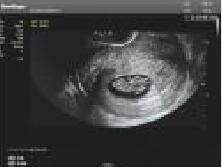

每次回院复诊都能感受到耿妈妈与王丝丝医生的用心照顾,2023年1月23日移植2枚囊胚,成功妊娠!